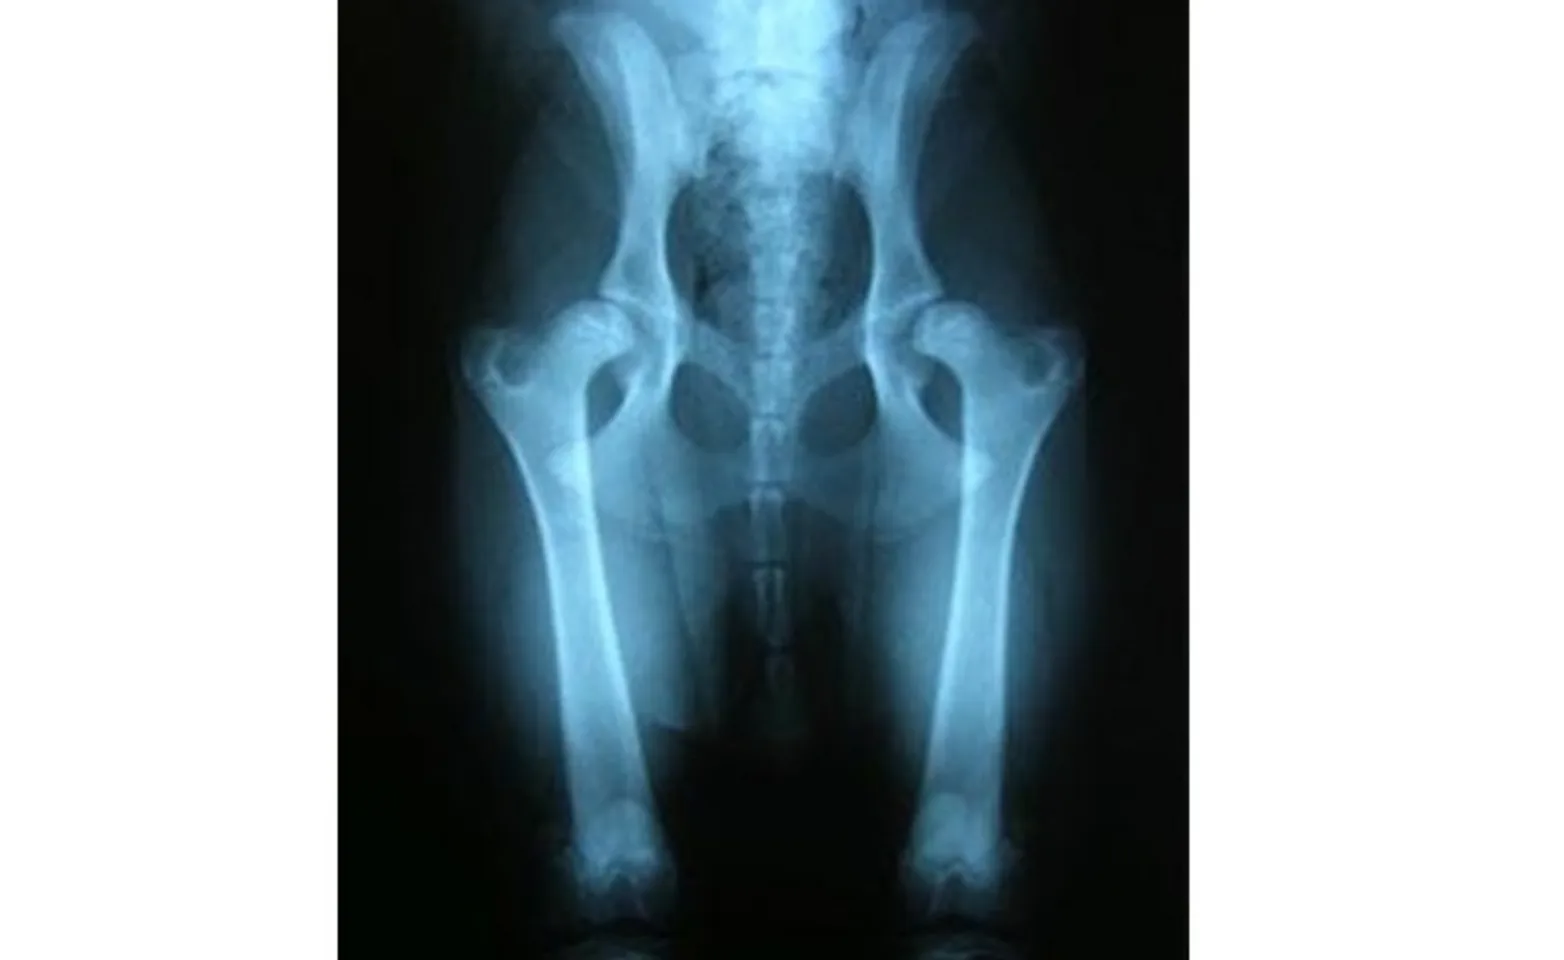

In the juvenile form of hip dysplasia, radiographs of the hips show a separation between the femoral head and acetabulum, indicating joint laxity (Figure 2). As the condition progresses, there may also be early signs of remodeling or flattening of the femoral head, and the acetabulum may become more shallow (Figure 3). In older dogs, there is often severe flattening of the femoral head, a shallow acetabulum, and signs of arthritis: abnormal bone formation, osteophytes (bone spurs), and collapse of the joint space (Figure 4).

Figure 2: Radiograph showing a young dog with mildly subluxated hips as a result of joint laxity seen in the juvenile form of hip dysplasia.